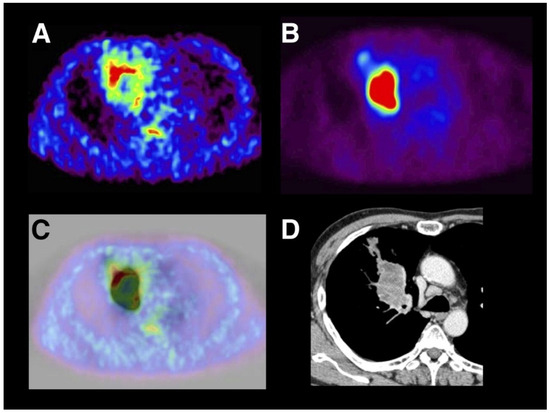

- Zegers, C.M.L.; van Elmpt, W.; Reymen, B.; Even, A.J.G.; Troost, E.G.C.; Ollers, M.C.; Hoebers, F.J.P.; Houben, R.M.A.; Eriksson, J.; Windhorst, A.D.; et al. In vivo quantification of hypoxic and metabolic status of NSCLC tumors using [18F]HX4 and [18F]FDG-PET/CT imaging. Clin. Cancer Res. 2014, 20, 6389–6397. [Google Scholar] [CrossRef] [PubMed]